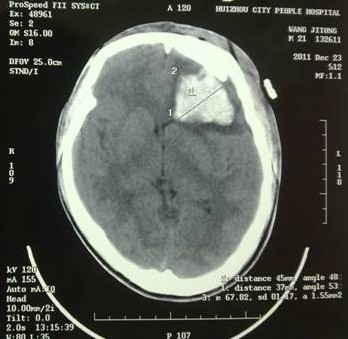

于是家屬慕名求助于我院余永強(qiáng)主任,在傷后第三天轉(zhuǎn)來我院。余永強(qiáng)主任主持術(shù)前討論,決定為患者施行微創(chuàng)手術(shù)清除血腫。通過CT掃描進(jìn)行術(shù)前精確定位,隨后在局麻下進(jìn)行微創(chuàng)手術(shù)。術(shù)中利用余主任設(shè)計(jì)研制的“e形微創(chuàng)手術(shù)定向儀”作引導(dǎo),將穿刺針準(zhǔn)確無誤置入血腫靶心,順利地清除了絕大部分血腫。術(shù)后復(fù)查頭顱CT,血腫清除超過90%(圖2)。憑借微創(chuàng)技術(shù),頭皮僅僅只需要一個(gè)直徑3毫米的小孔,通過一根高科技微創(chuàng)穿刺針,便可達(dá)到同樣的甚至更好的治療效果(圖3)。術(shù)后留置引流1天,第7天即痊愈出院。手術(shù)達(dá)到近乎“完美”的效果!患者親屬大為感慨微創(chuàng)手術(shù)的“神奇”,術(shù)后專程送來錦旗一幅――“微創(chuàng)手術(shù)顯神功” !(圖4)

圖2(2):術(shù)后2周復(fù)查,腦組織恢復(fù)良好。